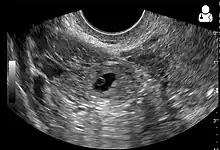

Transvaginal ultrasonography of an ectopic pregnancy, showing the field of view in the following image.

A "blob sign", which consists of the ectopic pregnancy. The ovary is distinguished from it by having follicles, whereof one is visible in the field. This patient had an intrauterine device (IUD) with progestogen, whose cross-section is visible in the field, leaving an ultrasound shadow distally to it.

Ultrasound image showing an ectopic pregnancy where a gestational sac and fetus has been formed.